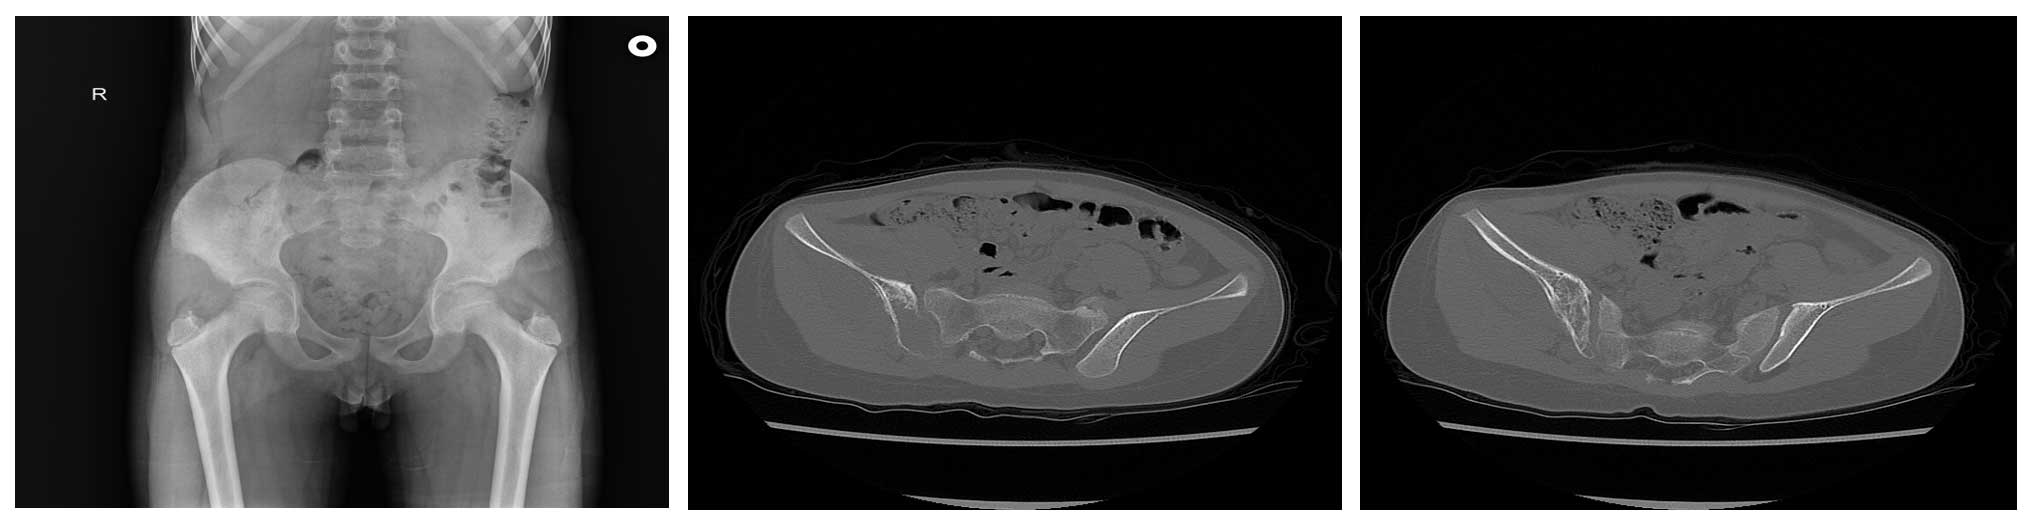

Ameliyat Öncesi: Röntgende sağ iliak kanatda düzensizlik, tomografide kemik harabiyeti ve periost reaksiyonu görülmekte.